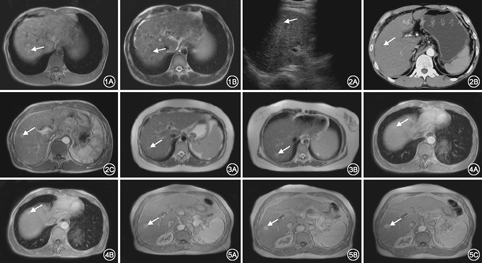

随访过程中,96例患者均行US、CT、MRI检查,共145个病灶,超声检出62个(42.6%),仅能提示占位;CT增强扫描检出90个(62.1%),典型结节恶变呈"快进快出"强化模式、假包膜、病灶进行性增大或短期数目增多;MRI及其随访过程中发现恶变结节138个(95.2%),表现为T1WI信号降低、T2WI信号增高、T2WI出现"结节套结节"征象、DWI信号增高、脂肪变性、强化方式改变、假包膜、进行性增大或短期病灶数目增多。

96例患者,145个恶变肝硬化结节,病灶呈圆形、类圆形为主,长径0.5~2.8 cm,平均长径1.5 cm。其中单发病例71例,多发病例25例。(1)超声检查:超声检出62个(62/145),阳性率42.8%。病灶内及周围树状广泛分布的血管彩色血流丰富,流速分布不均。52例出现门脉高压,门脉主干直径1.4~2.1 cm,脾静脉内径>0.8 cm。38例出现腹水。(2)CT检查:CT检出90个恶变结节,阳性率62.1%。增强扫描动脉期明显强化72个(4例出现结节中结节强化),门脉期、延迟期强化减退;部分乏血供病灶无明显动脉期强化,门脉期强化16个,延迟期仍为高密度2个。(3)MRI检查:MRI典型表现为T1WI呈高信号,T2WI呈低信号,增强扫描与周围肝实质强化方式相仿(图1)。阳性个数138个,阳性率95.2%。138个恶变结节中,5个直径<2 cm的病灶在T1WI和T2WI上为等信号,动脉期较均匀强化。T1WI呈高信号26个,等信号48个,低信号64个;T2WI病灶呈高信号为主,为101个,等信号24个,低信号13个;动态增强扫描呈典型"快进快出" 104个,"快进慢出" 23个。DWI高信号102例,T2WI、DWI同时呈高信号78例。MRI对肝硬化结节癌变内部成分的显示明显优于US、CT(图2)。3种监测方法方差分析F=57.694,P=0.000,组间存在显著性差异。MRI与CT、US比较差异有统计学意义(P=0.00)。

目前北美一些医学中心CT、MRI已经应用于肝癌高危患者随访,而不仅仅是超声阳性发现后对病灶进行定性诊断[17],AASLD建议对肝硬化病人定期MRI复查[18]。本研究发现以下征象高度提示肝硬化结节癌变:(1)T1WI信号降低;(2)T2WI信号持续增高;(3)T2WI表现为"结节中结节";(4)病灶出现脂肪变性;(5)动脉期病灶明显强化或病灶内结节状强化;(6)DWI呈高信号及DWI信号增高;(7)病灶出现延迟强化假包膜;(8)病灶短期随访进行性增大,尤其直径>3 cm,高度提示结节恶变;(9)病灶数进行性增加。此时,应缩短随访周期,磁共振3个月以内为宜,并及时行DSA检查或穿刺活检以期确诊。